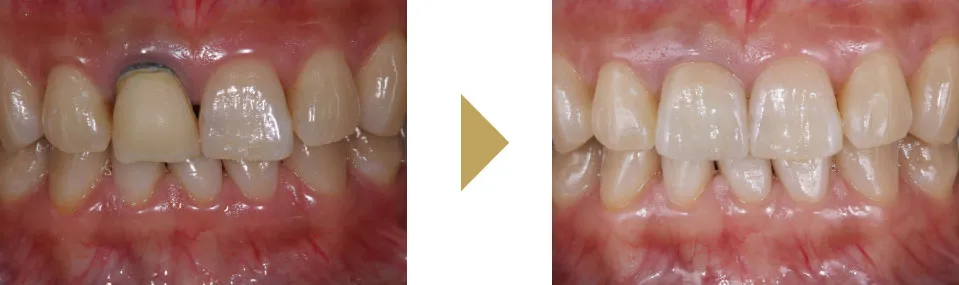

このような治療を行うことで、歯茎の黒ずみはほとんどわからなくなり、被せ物もセラミックで作り直すことで、患者様のご希望通りの自然な見た目を実現することができました。

以前、前歯の差し歯の変色と歯茎が黒くなってしまっている患者様の治療を行いました。

治療後には、自然と笑う回数が増え、今では口元を手で隠すこともなくなりました。

1本の差し歯で人生が変わる事だってあります。